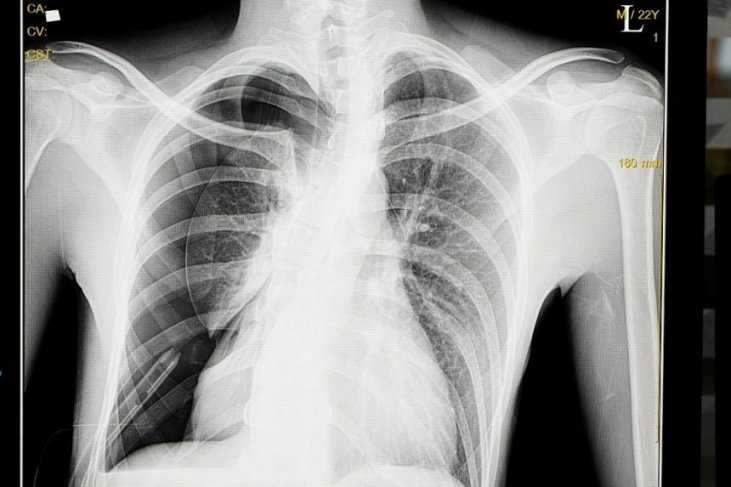

12/28/2018 · massa: kanker paru, kelenjar tiroid yg membesar, atau tumor mediastinal mediastinum kifoskoliosis hernia hiatal [8] b. bones and soft tissue. sehabis memastikan foto layak dibaca, bisa berpindah ke b buat melihat tulang yaitu menilai apakah simetris, apakah terdapat garis fraktur, lesi di tulang ataupun pertanda-tanda osteoporosis. X-rays are a type of radiation called electromagnetic waves. x-ray imaging creates pictures of the inside of your body. x-rays are a type of radiation called electromagnetic waves. x-ray imaging creates pictures of the inside of your body. X-rays use invisible electromagnetic energy beams to make images of internal tissues, bones, and organs on film. standard x-rays are done for many reasons, including diagnosing tumors or bone injuries. due to interest in the covid-19 vaccin.

Pasien yg menyajikan ke dokter menggunakan fraktur mungkin memiliki kanker tulang yang mendasari yg bisa diduga pada x ray. jika sinar x sugestif berdasarkan kanker tulang pasien dianggap seorang ahli untuk lebih lanjut penilaian dan manajemen. A chest kanker tulang x-ray x-ray looks at the structures and organs in your chest. learn more about how and when chest x-rays are used, as well as risks of the procedure. due to interest in the covid-19 vaccines, we are experiencing an extremely high call vol.

Pembentukan peripheral bony shell. foto x-ray thorax proyeksi ap/pa, buat melihat adanya metastasis paru menggunakan ukuran yang cukup besar , 2. computed tomography (ct) scan ct-scan dapat berguna buat menunjukkan detil lesi dalam tulang kompleks dan mendeteksi matriks ossifikasi minimal. selain. As you're sitting in the dentist's chair, you might be told you need a dental x-ray. here's what to expect with this painless procedure and why your dentist may recommend it. X-ray tulang umumnya nir berbahaya, tetapi paparan radiasi takaran akbar memang berisiko. sebagai model, terapi radiasi buat mengobati kanker dapat menyebabkan kanker baru berkembang di keliru satu tulang pada area perawatan. baca jua: ini tiga jenis kanker tulang premium.